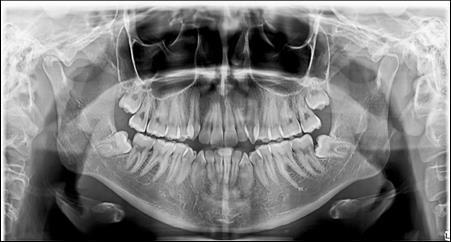

The panoramic radiograph showed bilateral mandibular third molars. The level of alveolar bone crest was within the normal range. (Figure 3)

Figure 3.Pretreatment panoramic X-ray